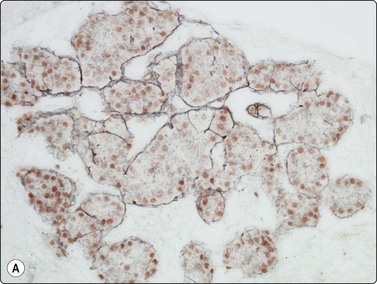

Normal structures (Fig. 10.1)

Cytologic features

Hepatocytes mainly in cohesive sheets; some smaller cell aggregates and few single-lying cells,

Kupffer cells and sinusoidal endothelial cells,

Bile duct epithelium.

Fig. 10.1 Hepatocytes

(A) Irregular cohesive sheet showing a trabecular arrangement (Pap, IP); (B) Cohesive groups of polygonal cells with abundant sometimes vacuolated granular cytoplasm (Pap, HP); (C) Cohesive cells with central round nuclei, granular cytoplasm and indistinct cell borders; note the small wedge-shaped Kupffer cell (arrow) (MGG, HP).

In smears, normal hepatocytes form irregular, cohesive sheets and narrow cords 1–2 cells thick (Fig. 10.1A). Single cells are infrequent. The cells are large, round or distinctly polygonal in outline with abundant granular cytoplasm, sometimes vacuolated, staining eosinophilic with H&E, blue with Papanicolaou or gray–blue with MGG (Fig. 10.1B). Nuclei are centrally located, round, with finely granular chromatin which is evenly distributed. Binucleate cells are common. Nucleoli are central and usually small although prominent. The cell membrane is indistinct. Normal hepatocytes may display mild to moderate anisokaryosis due to polyploidy, increasing with the patient’s age. Occasional nuclei may be very large in non-neoplastic liver tissue. Coarse, granular intracytoplasmic pigment is commonly present in hepatocytes. It stains green–black with MGG, brown with H&E and is probably lipofuscin rather than bile. Kupffer cells can usually be found and appear as single, bare, comma-shaped nuclei between the hepatocytes. Bile duct epithelial cells form small, regular monolayered sheets. They are palisaded when seen from the side. The cytoplasm is minimal, nuclear chromatin is granular and nucleoli are inconspicuous. These are few in number in samples from normal liver tissue.